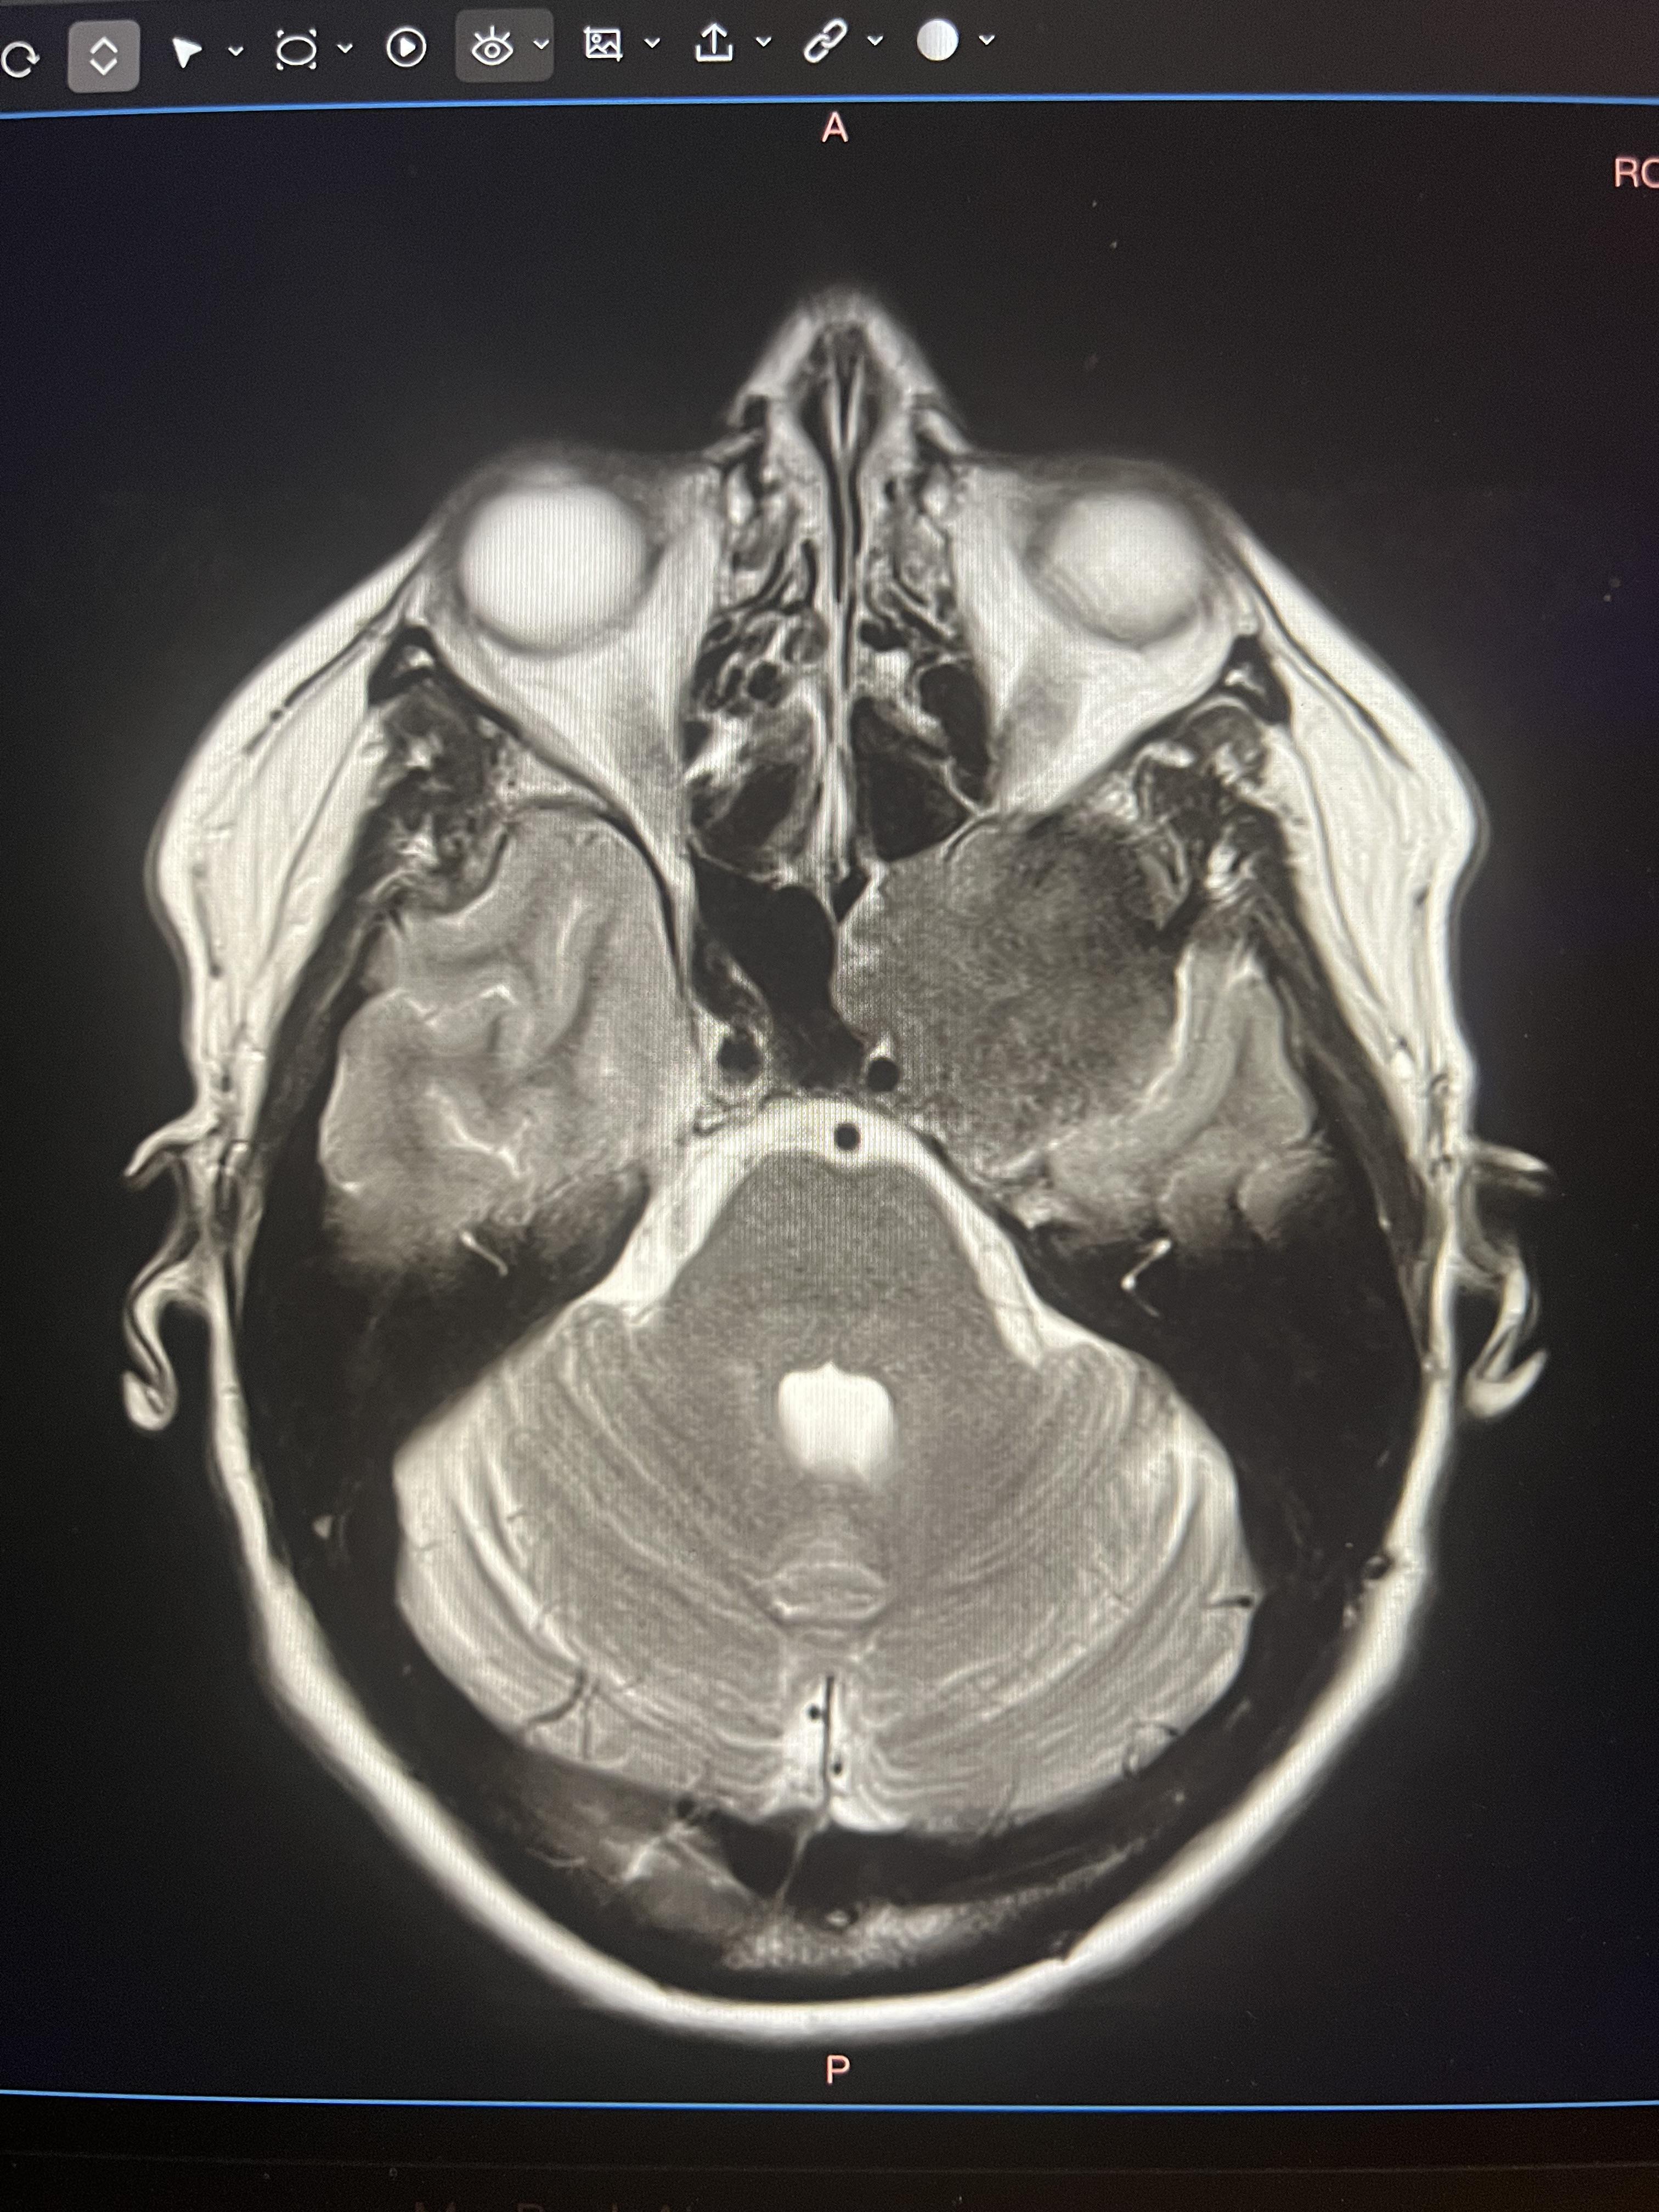

My tumour, a meningioma, was about 4-5cm, and had grown slowly over a decade. It is deep in a bit of the brain called the cavernous sinus, wrapped around my occipital nerve and trigeminal nerve.